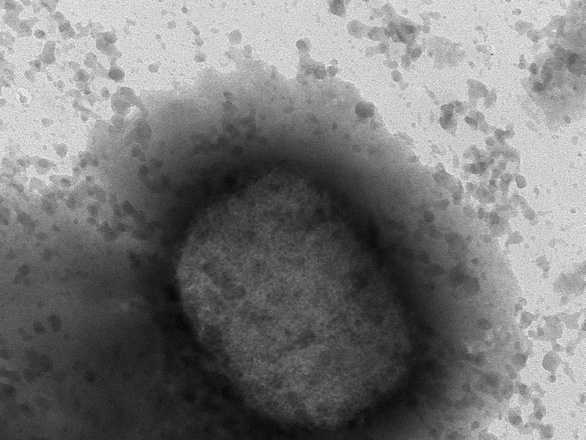

Nghiên cứu đầu tiên về các ca đậu mùa khỉ tại Anh cho thấy bệnh nhân có triệu chứng khác biệt đáng kể với các bệnh nhân trong những đợt bùng phát trước. Thông tin này được công bố trên tạp chí khoa học The Lancet ngày ngày 1/7 vừa qua.

Trong nghiên cứu này, các chuyên gia tiến hành phân tích tình trạng bệnh của 54 bệnh nhân mắc đậu mùa khỉ ở London, tất cả đều là nam có quan hệ đồng tính. Trong số này, chỉ có 2 người không biết mình đã tiếp xúc với người mắc bệnh, 25% số người này nhiễm virus HIV, 25% đã mắc bệnh lây nhiễm qua đường tình dục khi mắc đậu mùa khỉ. Tất cả các bệnh nhân đều có các vết tổn thương ngoài da, trong đó có 94% xuất hiện ở vùng bộ phận sinh dục và hậu môn.

Cũng theo nghiên cứu, chỉ 57% số ca bệnh có triệu chứng sốt, thấp hơn mức từ 85-100% ghi nhận ở các đợt bùng phát dịch bệnh trước. Các đợt bùng phát trước cũng ghi nhận tỷ lệ bệnh nhân bị tổn thương da ở các vùng chi, mặt và cổ cao hơn trong khi 75% số ca bệnh tại Anh trong nghiên cứu trên ghi nhận tổn thương da ở một hoặc hai vùng, chủ yếu ở trên hoặc xung quanh bộ phận sinh dục. Các bệnh nhân ở Anh cũng chủ yếu xuất hiện các triệu chứng nhẹ, sốt không quá 3 ngày và chỉ có 5 người phải nhập viện.